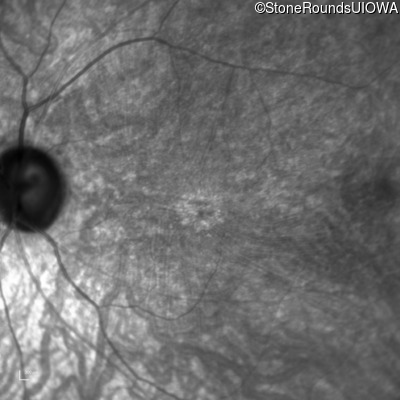

Infrared Fundus Photograph - Right - 20/100 -1 sc

Exemplar